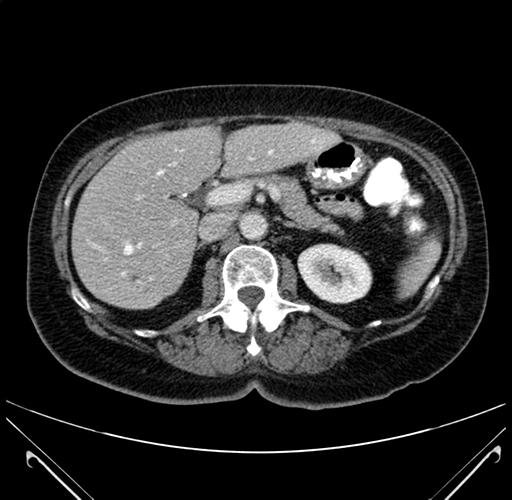

Coronal Venous